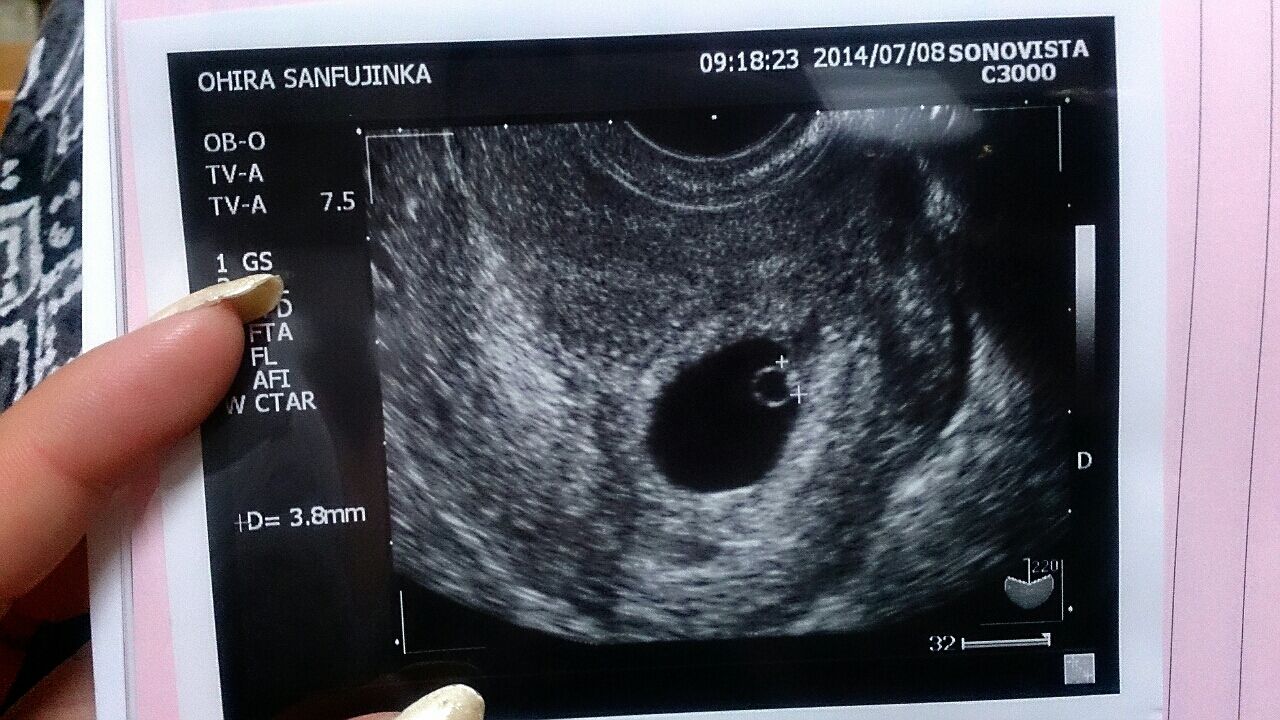

妊娠5週目 胎嚢のエコー写真 つわり症状や流産のこと 妊娠初期 All About

妊娠6週 エコーで赤ちゃんの心拍確認 つわりの症状や過ごし方 ままのて

妊娠6週目 心拍確認 エリのハッピーベビーダイアリー

助産師監修 妊娠6週目 妊娠2ヶ月 エコー写真 心拍確認やつわり 出血について

妊娠6週目 6w0d 6d のエコー写真とエピソード 妊娠2ヶ月 Cozre コズレ 子育てマガジン

妊娠6週目 エコー写真 胎芽や胎嚢大きさ 心拍確認や気になる流産 妊娠初期 All About

6w4d心拍確認できた エコーで確認した胎嚢のサイズや胎芽の大きさ つわりまとめ 晩婚だけど幸せ みゃーのアラフォー結婚生活ブログ